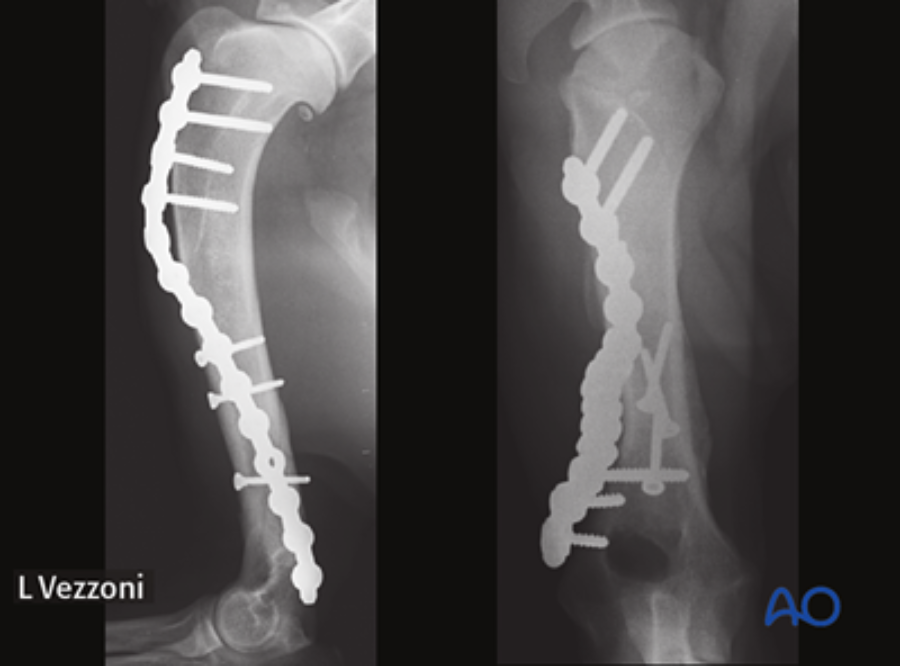

The module on this anatomical area was authored by Martin Unger (Germany). Matthew J Allen (UK) and Aldo Vezzoni (Italy) acted as editors.

It encompasses both nonsurgical and surgical management techniques, providing detailed insights into the utilization of plates, intramedullary pins, and interlocking nails for fixation. Additionally, it offers supplementary reading materials that highlight the anatomical distinctions between dogs and cats, as well as the most prevalent complications that arise during humeral shaft fracture management.

Matthew Allen: For me, the most interesting part of the module relates to the use of locking plates, especially in the context of minimally invasive surgical approaches. This method’s advantages include a combination of periosteal preservation and superior stability, which is achievable by locking the screw head directly into the plate. Where this approach is indicated, it is an excellent option for humeral shaft and humeral condylar fractures.

Once an initial version was completed, the module underwent a rigorous evaluation process. Esteemed professionals in the field, including Amy Kapatkin (executive editor), Aldo Vezzoni (general editor for thoracic limb), and Matthew Allen (AO VET’s incoming executive editor), meticulously reviewed it. Their invaluable insights and recommendations, including the addition of further case examples, were thoughtfully incorporated. This phase of review and quality control ensured a robust and comprehensive module even before the final version was produced.